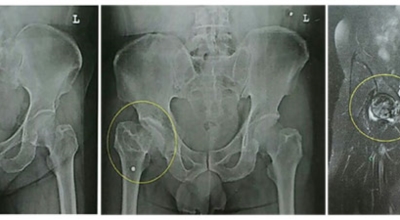

각별히 젊은 남성에게 잘 발생하며 엉덩이와 골반 주위에 뻐근한 통증이 동반되며 정상적인 보행이 되지 않고 절뚝거리는 증상이 나타난다면 대퇴골두 무혈성 괴사일 가능성이 있답니다. 이 증상은 괴사 부위의 골절이 발생되어 고관절 손상으로 이어지면 발생하는 증상으로 아직까지 정확한 원인은 규명하기 힘드나 과음이나 고지혈증, 스테로이드 과남용이 영향을 줄 수 있어요.